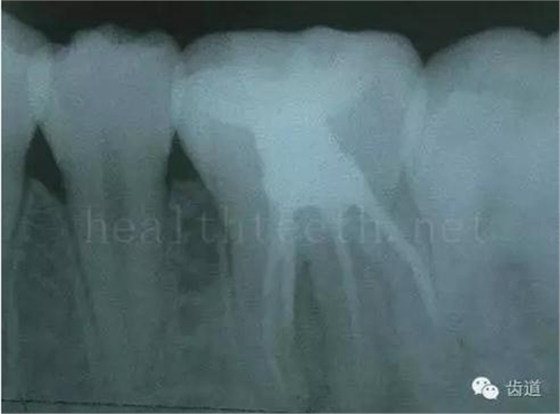

長期戴活動義齒不當或是戴不良修復(fù)義齒造成的口腔粘膜潰瘍,應(yīng)該引起高度警惕,因為這種潰瘍?nèi)菀装┳?/span> 黑毛舌 舌息肉,該患者同時伴有胃、食管息肉,后來看內(nèi)科了,具體情況不詳 四、孩子的牙齒問題 乳牙未退,牙根穿出牙齦對上唇粘膜造成刺激 乳牙滯留,也是孩子在退牙過程中最容易遇到的問題 五、牙齒發(fā)育上的問題 變色牙 氟斑牙 釉質(zhì)發(fā)育不全 四環(huán)素牙 牙神經(jīng)治療后的牙齒變色 10歲孩子剛剛萌出的牙齒變色 2、埋伏牙 左上乳3滯留,恒3未見萌出,曲面斷層片顯示牙齒埋伏 通過CT片確定埋伏牙齒具體的位置,顯示距離左側(cè)上頜竇很近,偏唇側(cè),這為手術(shù)定位提供了方便 手術(shù)中切斷、完整拔出,未損傷上頜竇 其他埋伏牙 3、多生牙 病例1 病例2 病例3,同時多生兩顆牙齒 4、各種畸形牙 畸形過小牙 融合牙:恒牙和乳牙都可以發(fā)生融合的情況(兩顆牙齒長在了一起) 畸形中央尖:在牙齒的中央,兩個牙尖之間又多長出一個牙尖,由于進食的磨耗很容易造成磨穿,神經(jīng)就會與外界相通,出現(xiàn)牙髓炎的癥狀 六、牙齒的外傷 牙冠折斷 牙根折斷 烤瓷牙打樁修復(fù)后牙根折斷 外傷后牙齒的全脫位,應(yīng)該保留牙齒盡早做再植手術(shù) 七、牙齒的慢性損傷 牙頸部楔狀缺損 牙冠劈裂及完整拔除后的情況 牙根縱裂及拔除后的情況 牙隱裂,牙齒表面有肉眼看不到的裂紋,細菌通過其進入牙髓,容易出現(xiàn)牙髓炎癥狀,嚴重可以造成牙齒的劈裂 這是一位來中國學(xué)習(xí)的俄羅斯大學(xué)生的牙齒,已經(jīng)做過了根管治療,牙齒咬合面有隱裂,通過鋼絲結(jié)扎固定,做鑄造金屬冠修復(fù)。 八、牙髓炎、根尖周炎 下面圖片都是慢性根尖周炎的病例,有了齲齒,進一步發(fā)展就是牙髓炎,如果此時沒有得到及時的治療,疾病會逐漸發(fā)展破壞到根尖的骨質(zhì),將骨質(zhì)破壞后就在牙齦上出現(xiàn)一個膿瘺,此時患者不再感覺到牙齒的疼痛了,往往忽視了治療,但是這種不痛并不是疾病好轉(zhuǎn)了,而是因為疾病的炎性滲出得到了引流,這個膿瘺會出現(xiàn)有時候變大了,有時候又變小了,但是如果不治療是不會自己愈合的,只有經(jīng)過完善的根管治療后才有好轉(zhuǎn)的可能,但是在疾病的治療中時間是起決定作用的,時間拖得越晚,好轉(zhuǎn)的可能性越小,經(jīng)過根管治療后如果膿瘺還是沒有消失,就需要做根尖刮治術(shù),如果仍然沒有好轉(zhuǎn),就只能做根尖切除術(shù)了,這對牙齒的穩(wěn)固是不利的。下面圖片中在膿瘺中插入了一個牙膠尖,是我們做根管充填用的材料,是非常軟的,就是在口腔牙齦瘺管的地方插進去,通過拍牙片可以清晰地看到它到達的位置,從而確定發(fā)病的牙齒,此處是為了讓大家看得更清楚。 門牙兩個膿瘺 烤瓷牙修復(fù)后牙齦出現(xiàn)兩個膿瘺,插入牙膠尖,牙片顯示牙膠尖到達的位置就是根尖炎癥的位置,根尖骨質(zhì)密度降低(發(fā)黑的地方) 牙齒根尖膿瘺,治療前、中、后的圖片對照,完善根管治療后膿瘺明顯消失了 牙髓炎和根尖炎治療的關(guān)鍵就是根管治療 合格的根管充填治療 不良的根管充填治療 九、關(guān)于智齒(第八顆牙) 四顆長不出來的智齒 智齒反復(fù)發(fā)炎造成的頰瘺,膿腫切開引流后面部會留疤 智齒造成的頜骨囊腫,手術(shù)切除后需要植骨 十、各種錯合畸形 開合 深覆合 深覆蓋,上頜前突 反合(地包天) 牙齒排列擁擠 來源:牙醫(yī)愛看的 KQ88口腔醫(yī)學(xué)網(wǎng)